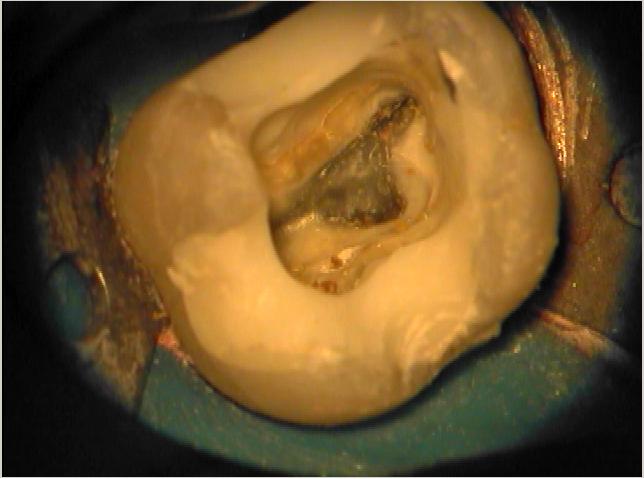

Klinische Situation

Entsprechende klinische Situation mit den zunächst dargestellten Kanalsystemen (p, mb1 und db)